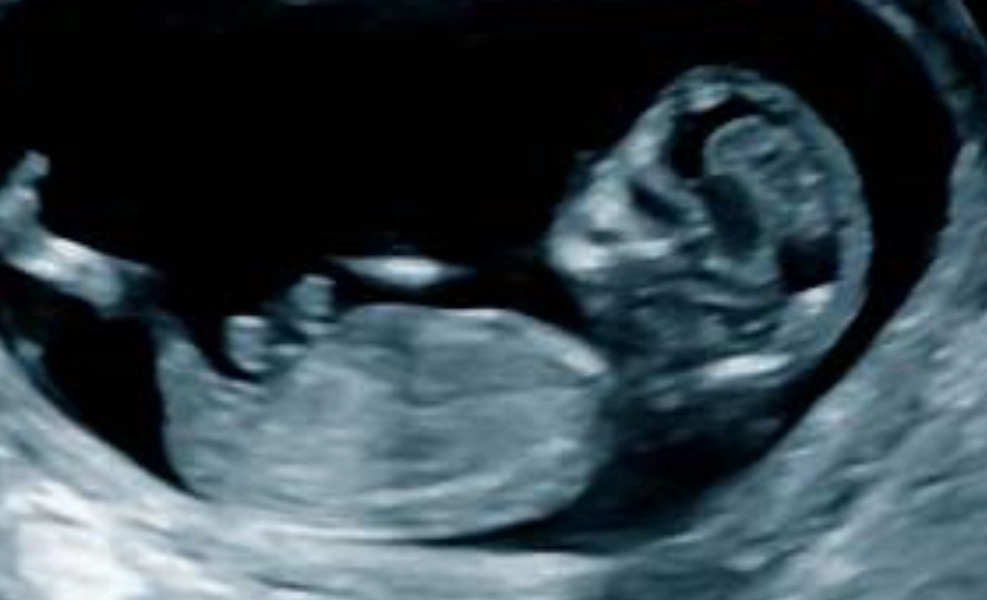

Many have the nuchal translucency (NT) scan around now. It's an ultrasound that measures fluid at the back of the baby's neck. Combined with a blood test, it assesses the risk for certain chromosomal conditions. It's also usually the first time you see your baby looking like a baby, not a little blob. They might be bouncing around.